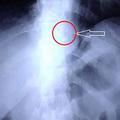

Pojedel je zobno protezo

Moški, ki je zaradi kašlja in stiskanja v prsih šel k zdravniku, je presenečeno ugotovil, da je razlog del zobne protez…